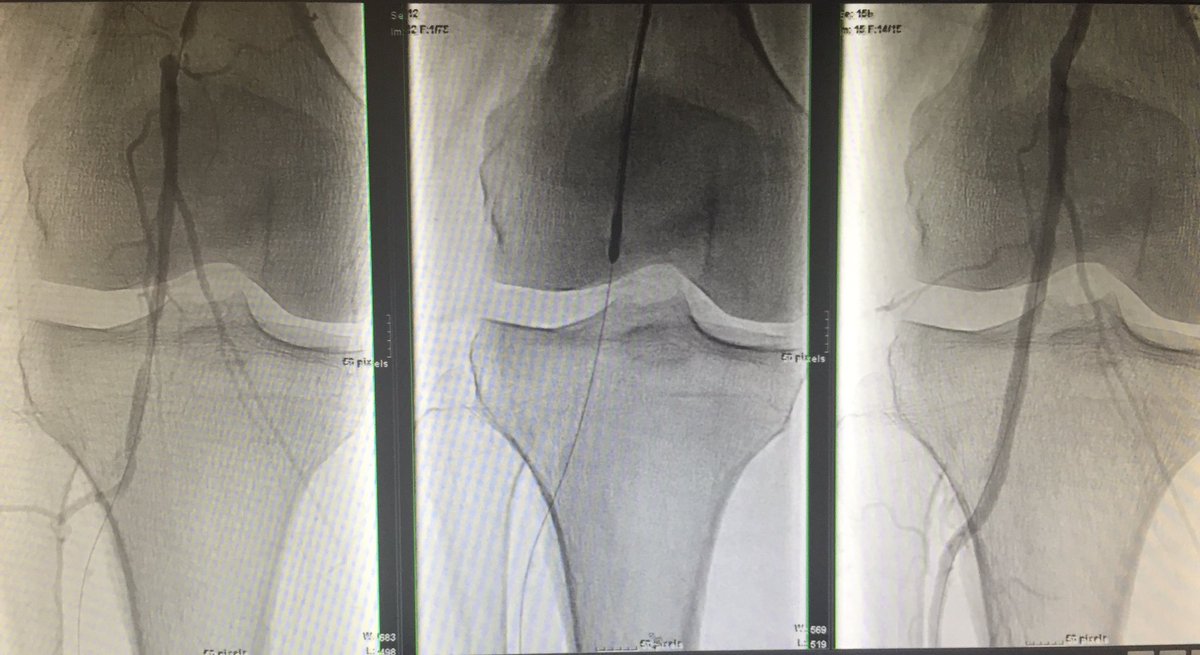

#vesselprep #Jetstream #DCB #palpablepulse #nostent Mount Sinai IR Endovascular Today Jeff Mirviss